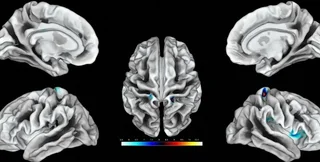

Ділянки мозку, що відповідають за клітор, виділені кольором. | Фото: ScienceAlert

Дослідники виявили ділянки мозку, які відповідають за реакцію на дотик до геніталій жінок. Виявилося, що вони розвиненіші в тих, хто займається сексом частіше.

Під час дослідження проводилася стимуляція клітора 20 дорослих жінок, під час якої сканування мозку здійснювалося за допомогою функціональної магнітно-резонансної томографії. Ученим вперше вдалося нанести на карту ділянки мозку, які відповідають за реакцію на дотик до геніталій у жінок. За словами дослідників, ці результати можна використовувати для лікування жінок, які страждають від сексуальної дисфункції, повідомляє ScienceAlert.

Соматосенсорна кора головного мозку отримує та обробляє інформацію про відчуття, що виходить з усього тіла. Кожна частина тіла відповідає окремій ділянці кори головного мозку та утворює репрезентативну карту. Але досі було незрозуміло, які ділянки відповідають за жіночі геніталії.

Стимулювання клітора відбувалося 8 разів поспіль протягом 10 секунд з 10-секундними перервами. У результаті сканування ділянок мозку вчені визначили, які саме з них відповідають за жіночі геніталії. Також учені з'ясували, що у жінок, які мають частіші сексуальні контакти, ці ділянки збільшені в розмірах.